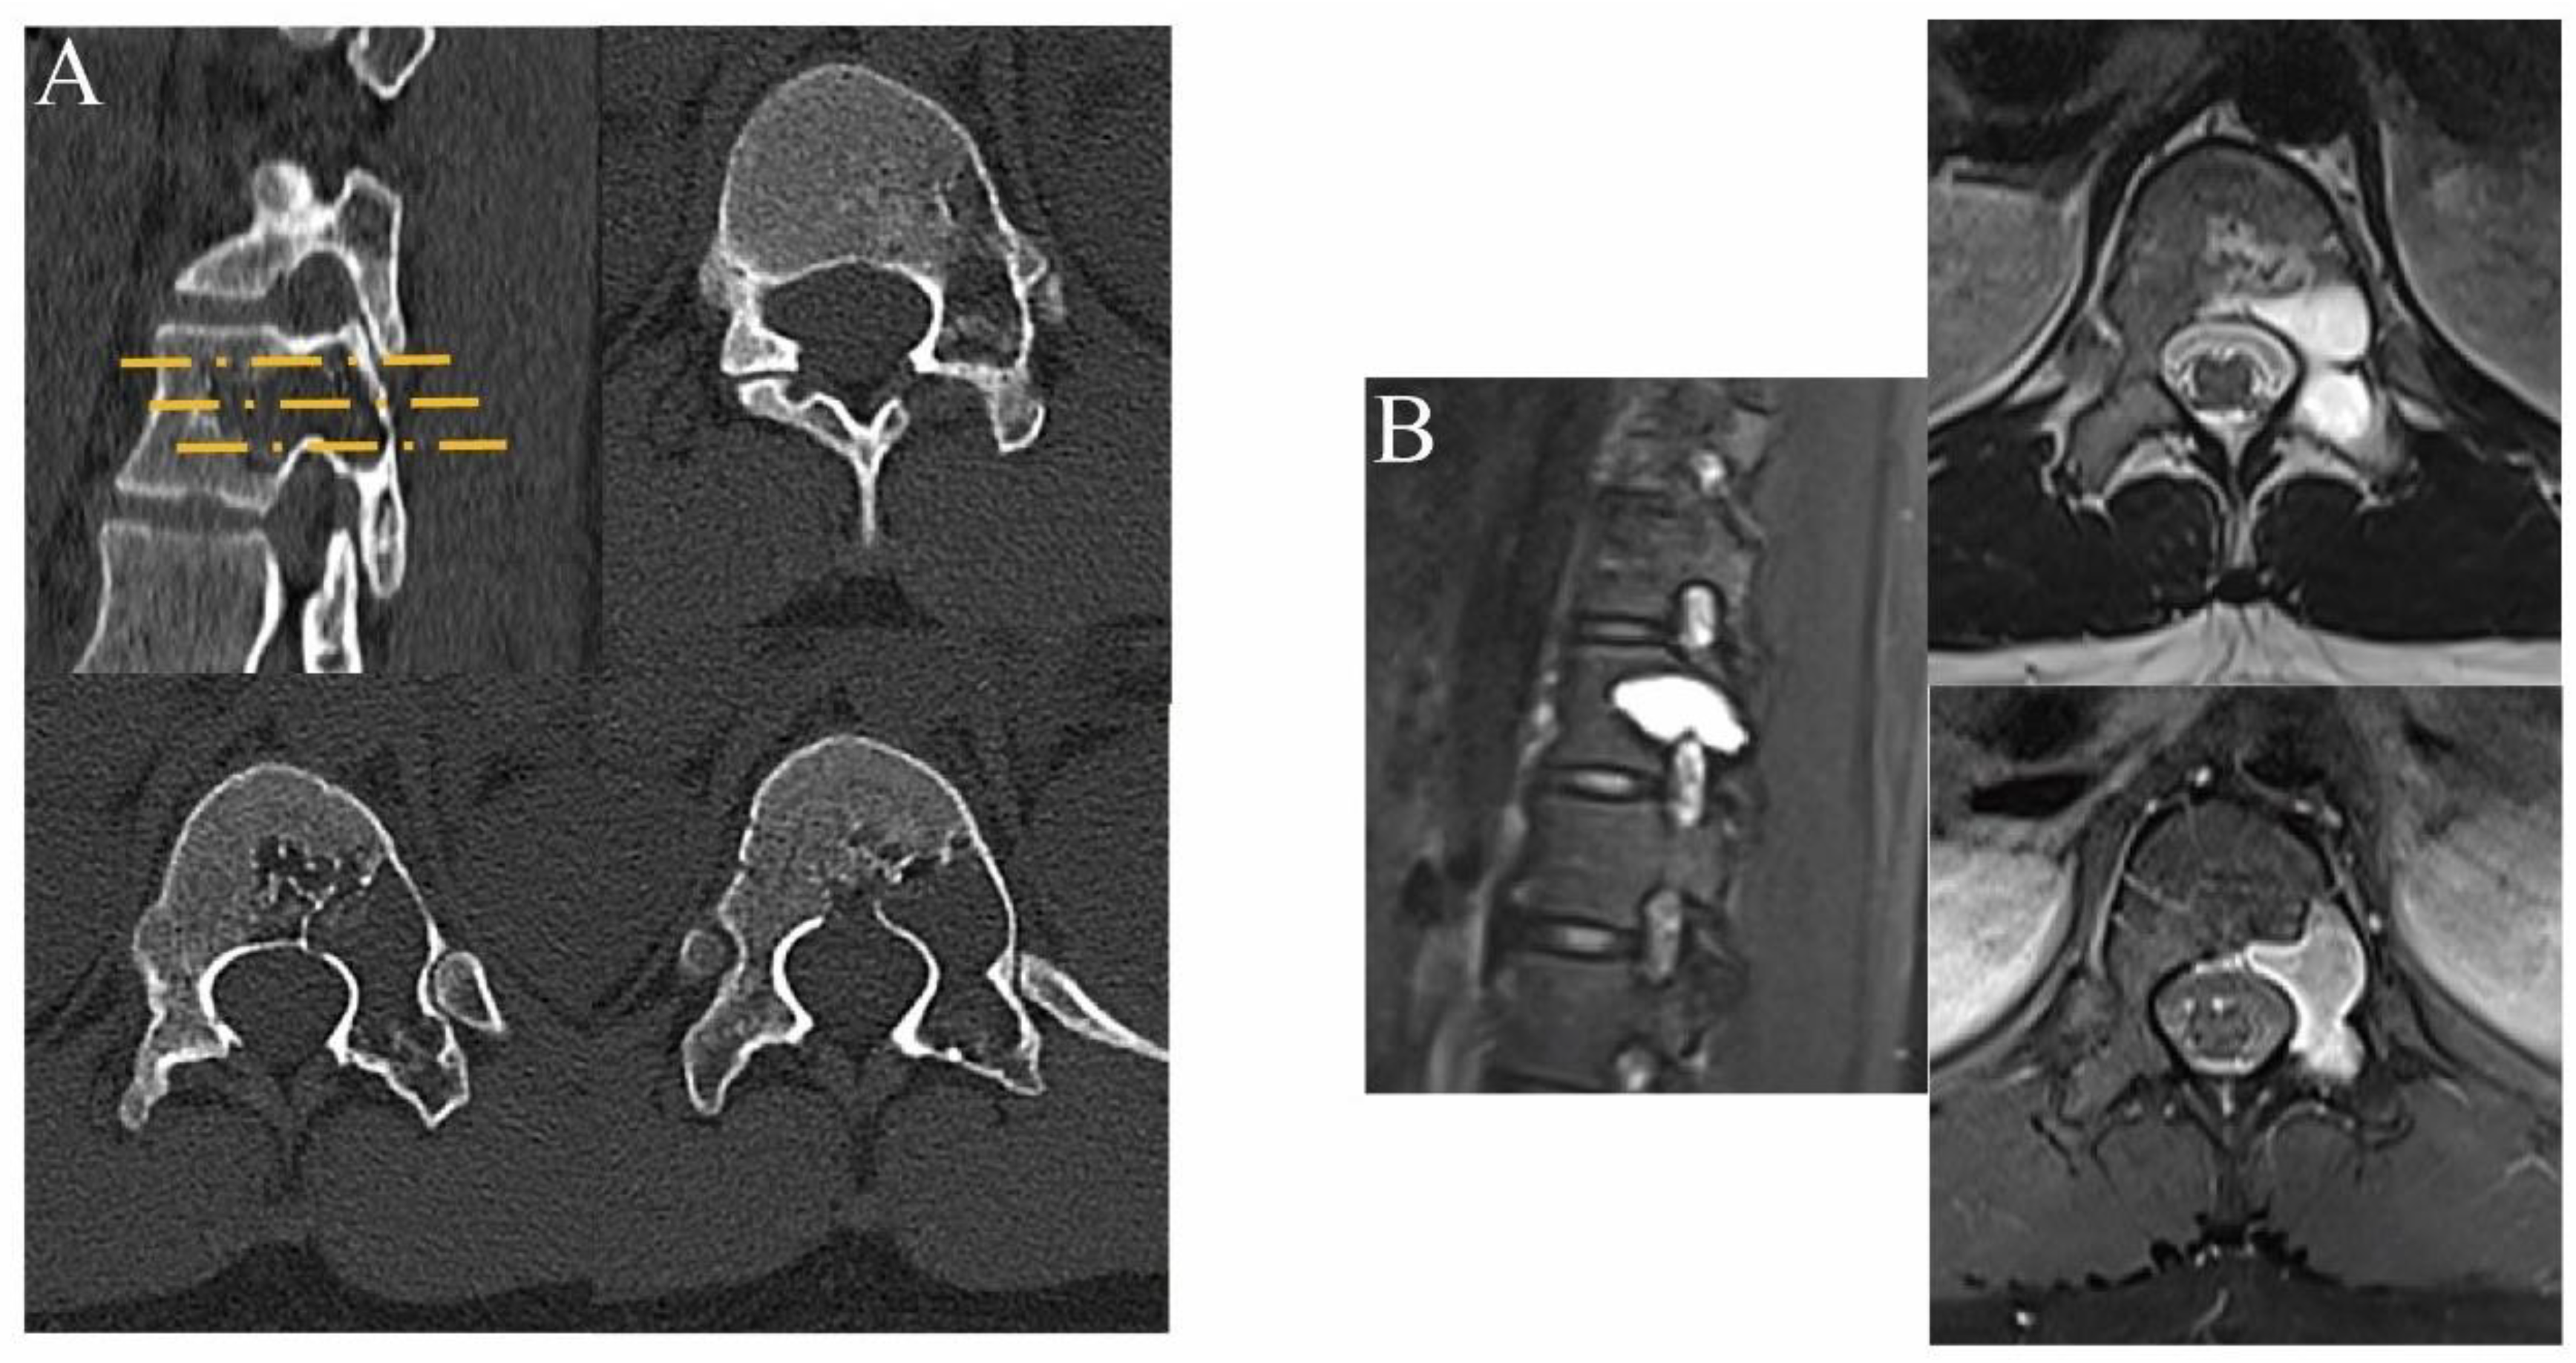

2. Materials and Methods

2.1. Preoperative Preparations

2.2. Surgical Technique